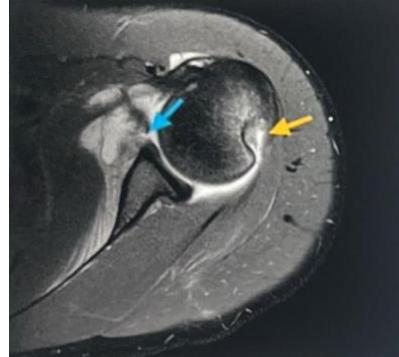

| For Glenohumeral joint: | |

o Feel the coracoid, go lateral to it from anterior![]() ![]() Posterior glenohumeral injection | |